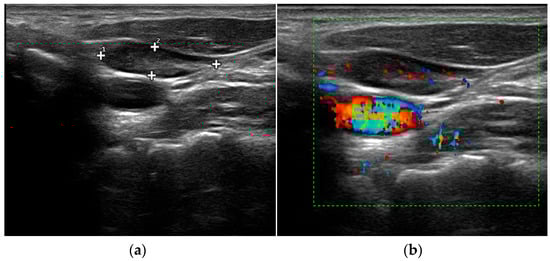

- Mohammadi, A.; Moloudi, F.; Ghasemi-rad, M. The role of colour Doppler ultrasonography in the preoperative localization of parathyroid adenomas. Endocr. J. 2012, 59, 375–382. [Google Scholar] [CrossRef]

- Vitetta, G.M.; Ravera, A.; Mensa, G.; Fuso, L.; Neri, P.; Carriero, A.; Cirillo, S. Actual role of color-doppler high-resolution neck ultrasonography in primary hyperparathyroidism: A clinical review and an observational study with a comparison of (99m)Tc-sestamibi parathyroid scintigraphy. J. Ultrasound. 2019, 22, 291–308. [Google Scholar] [CrossRef]

- Liu, H.; Liao, Q.; Wang, Y.; Hu, Y.; Zhu, Q.; Wang, L.; Liu, Q.; Li, J.; Jiang, Y. A new tool for diagnosing parathyroid lesions: Angio plus ultrasound imaging. J. Thorac. Dis. 2019, 11, 4829–4834. [Google Scholar] [CrossRef]